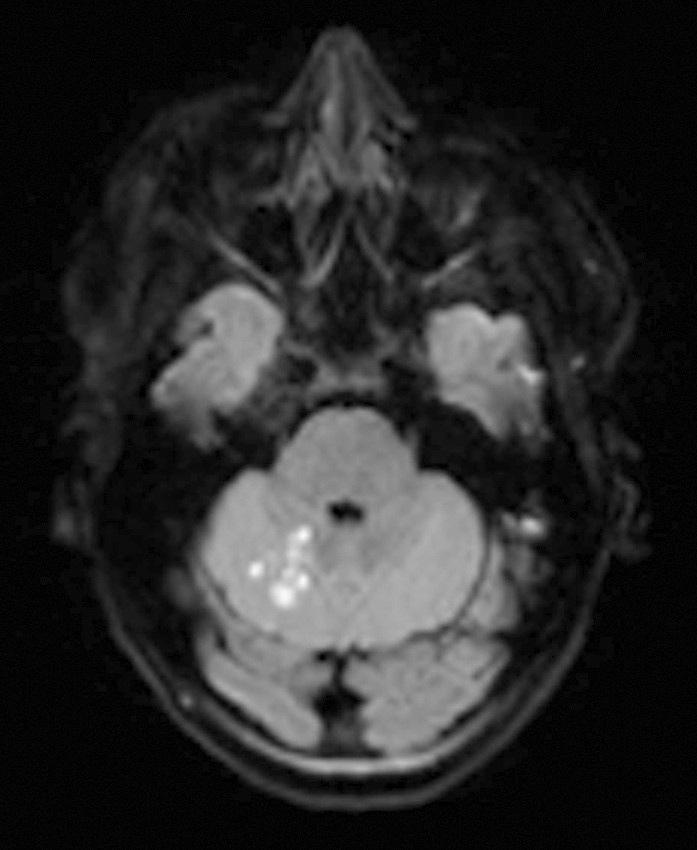

De påfølgende dagene opplevde pasienten gjentatte episoder med taleforstyrrelser og tyngdefølelse i høyre arm, i tillegg til varierende svimmelhet, ustøhet og hodepine. Nevrologisk undersøkelse viste redusert finmotorikk i høyre hånd. Ny MR-undersøkelse (seks dager etter den forrige) viste ferske infarktforandringer i høyre lillehjernehemisfære (figur 1).